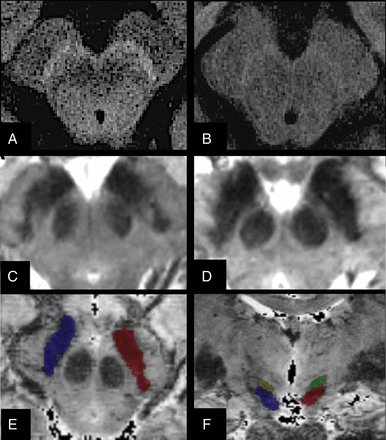

For NM images, contours of the SN were manually drawn around the area of high signal intensity twice by each blinded rater. The concordance between the segmentations was good (Dice similarity coefficient = 0.8). This 3T NM ROI primarily corresponded to the substantia nigra pars compacta.19 For 3T T2WI and 7T T2*WI, the SN was defined as the area of hypointensity ventral to the red nucleus and dorsal to the cerebral peduncle, primarily corresponding to the SN pars reticulata (Fig 1).19 The SN was separated from the subthalamic nucleus by a small notch on its lateral and anterior borders. The subthalamic nucleus was also segmented to avoid any error. All examiners were blinded to the subject's clinical status.

Segmentation of ROIs. Axial brain stem slices in a healthy volunteer (A) and a patient with Parkinson disease (B) show reduction of the neuromelanin signal intensity in the substantia nigra of the patient. Axial T2*WI 7T slices show dorsal nigral hyperintensity in a HV (C), which is absent in the patient with PD (D). T2WI axial (E) and coronal (F) images of the SN in a HV show T2-based segmentation of the SN.